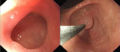

This category contains images taken at the time of endoscopy of the GI tract, using esophagogastroduodenoscopy, colonoscopy, double-balloon enteroscopy, or ERCP.